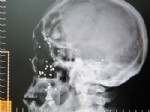

28 Ocak 2013 Pazartesi 12:01:1554 yıldır böyle yaşıyor!

Çocukluğunda geçirdiği silah kazasında yüzüne isabet eden 38 saçmayla 54 yıldır birlikte yaşıyor.

28 Ocak 2013 Pazartesi 11:58:28Yüzüne isabet eden saçmalar hayat ortağı oldu

Kahramanmaraşlı Hüseyin Akgemci, çocukluğunda geçirdiği silah kazasında yüzüne isabet eden 38 saçmayla 54 yıldır birlikte yaşıyor. Durumu